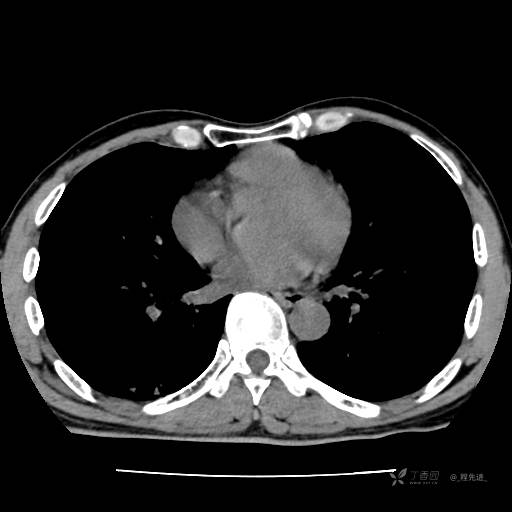

2月特别精彩病例|咳嗽、咳痰20余天,典型病例分享【结果已公布】

患者年龄:51岁

主诉:咳嗽、咳痰20余天

简要病史:20余天前开始出现咳嗽、咳痰症状,阵发性刺激性咳,白色粘痰,不易咳出,无发热,无咯血,无恶心、呕吐等不适,未诊治,咳嗽、咳痰症状持续存在。

体格检查:T:36.3 ℃ P:79 次/分 R:20 次/分 BP:128/64 mmHg,神志清楚,呼吸平稳,双肺呼吸音粗,右下肺闻及细湿性啰音。心率79次/分,节律整齐,各瓣膜听诊区未闻及病理性杂音。腹部未见异常,双下肢无水肿。

辅助检查:我院门诊胸部CT示:如下。心电图:窦性心律;正常心电图。